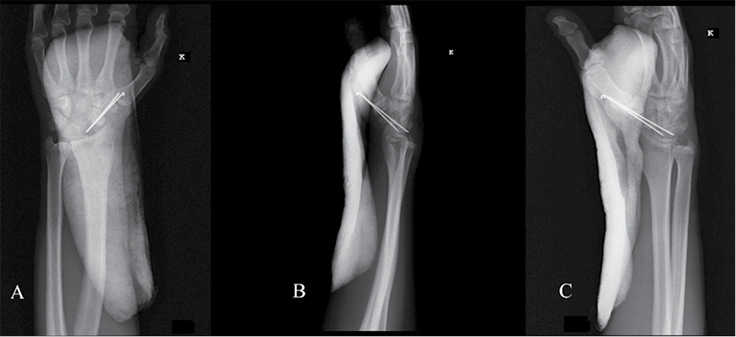

Skubiai atlikus riešo sąnario kompiuterinę tomografiją, nustatytas skeveldrinis laivelio proksimalinio galo lūžis, stipinkaulio distalinio dorzalinio krašto intrasąnarinis lūžis ir smulki mėnulio avulsija (žr. 1 pav.).

1 pav. Kairiojo riešo kompiuterinės tomografijos vaizdai prieš operaciją